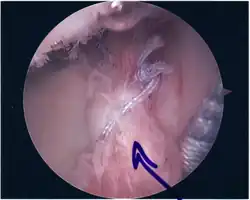

Following inspection and determination of the extent of injury, the basic labrum repair is as follows.

- The glenoid and labrum are roughened to increase contact surface area and promote re-growth.

- Locations for the bone anchors are selected based on number and severity of tear. A severe tear involving both SLAP and Bankart lesions may require seven anchors. Simple tears may only require one.

- The glenoid is drilled for the anchor implantation.

- Anchors are inserted in the glenoid.

- The suture component of the implant is tied through the labrum and knotted such that the labrum is in tight contact with the glenoid surface.